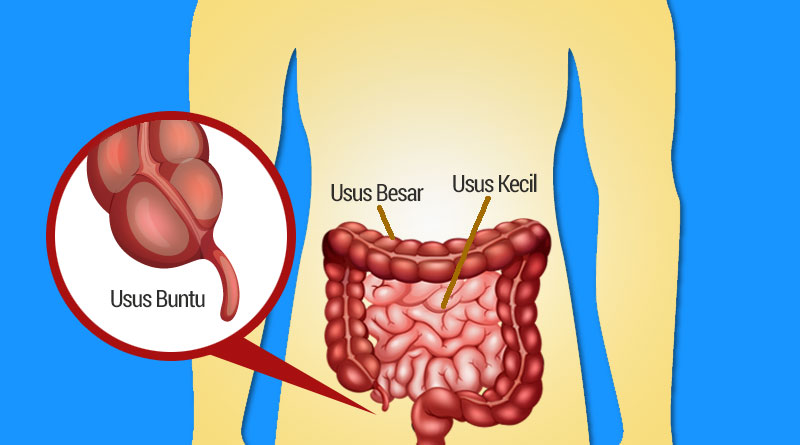

Cari Tahu Letak Dan Penyebab Usus Buntu

Cari Tahu Letak Dan Penyebab Usus Buntu